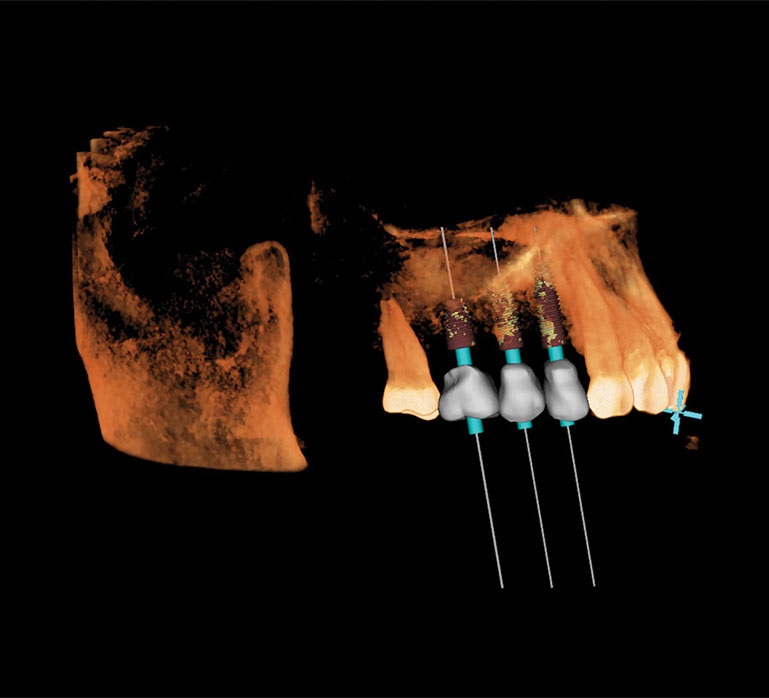

Recently, I placed three implants in Teeth 3, 4 and 5 in conjunction with a sinus lift. Implants in such close proximity to one another can be a challenge even for a specialist. By using the preplanning software, I virtually placed the implants precisely where I wanted them to go, as shown in Figs. 7, 8 and 9. I was thrilled with the outcome. As you can see on the X-ray in Fig. 10, the implants were placed precisely according to the plan.

Fig. 9: 3D plan shows axial view.